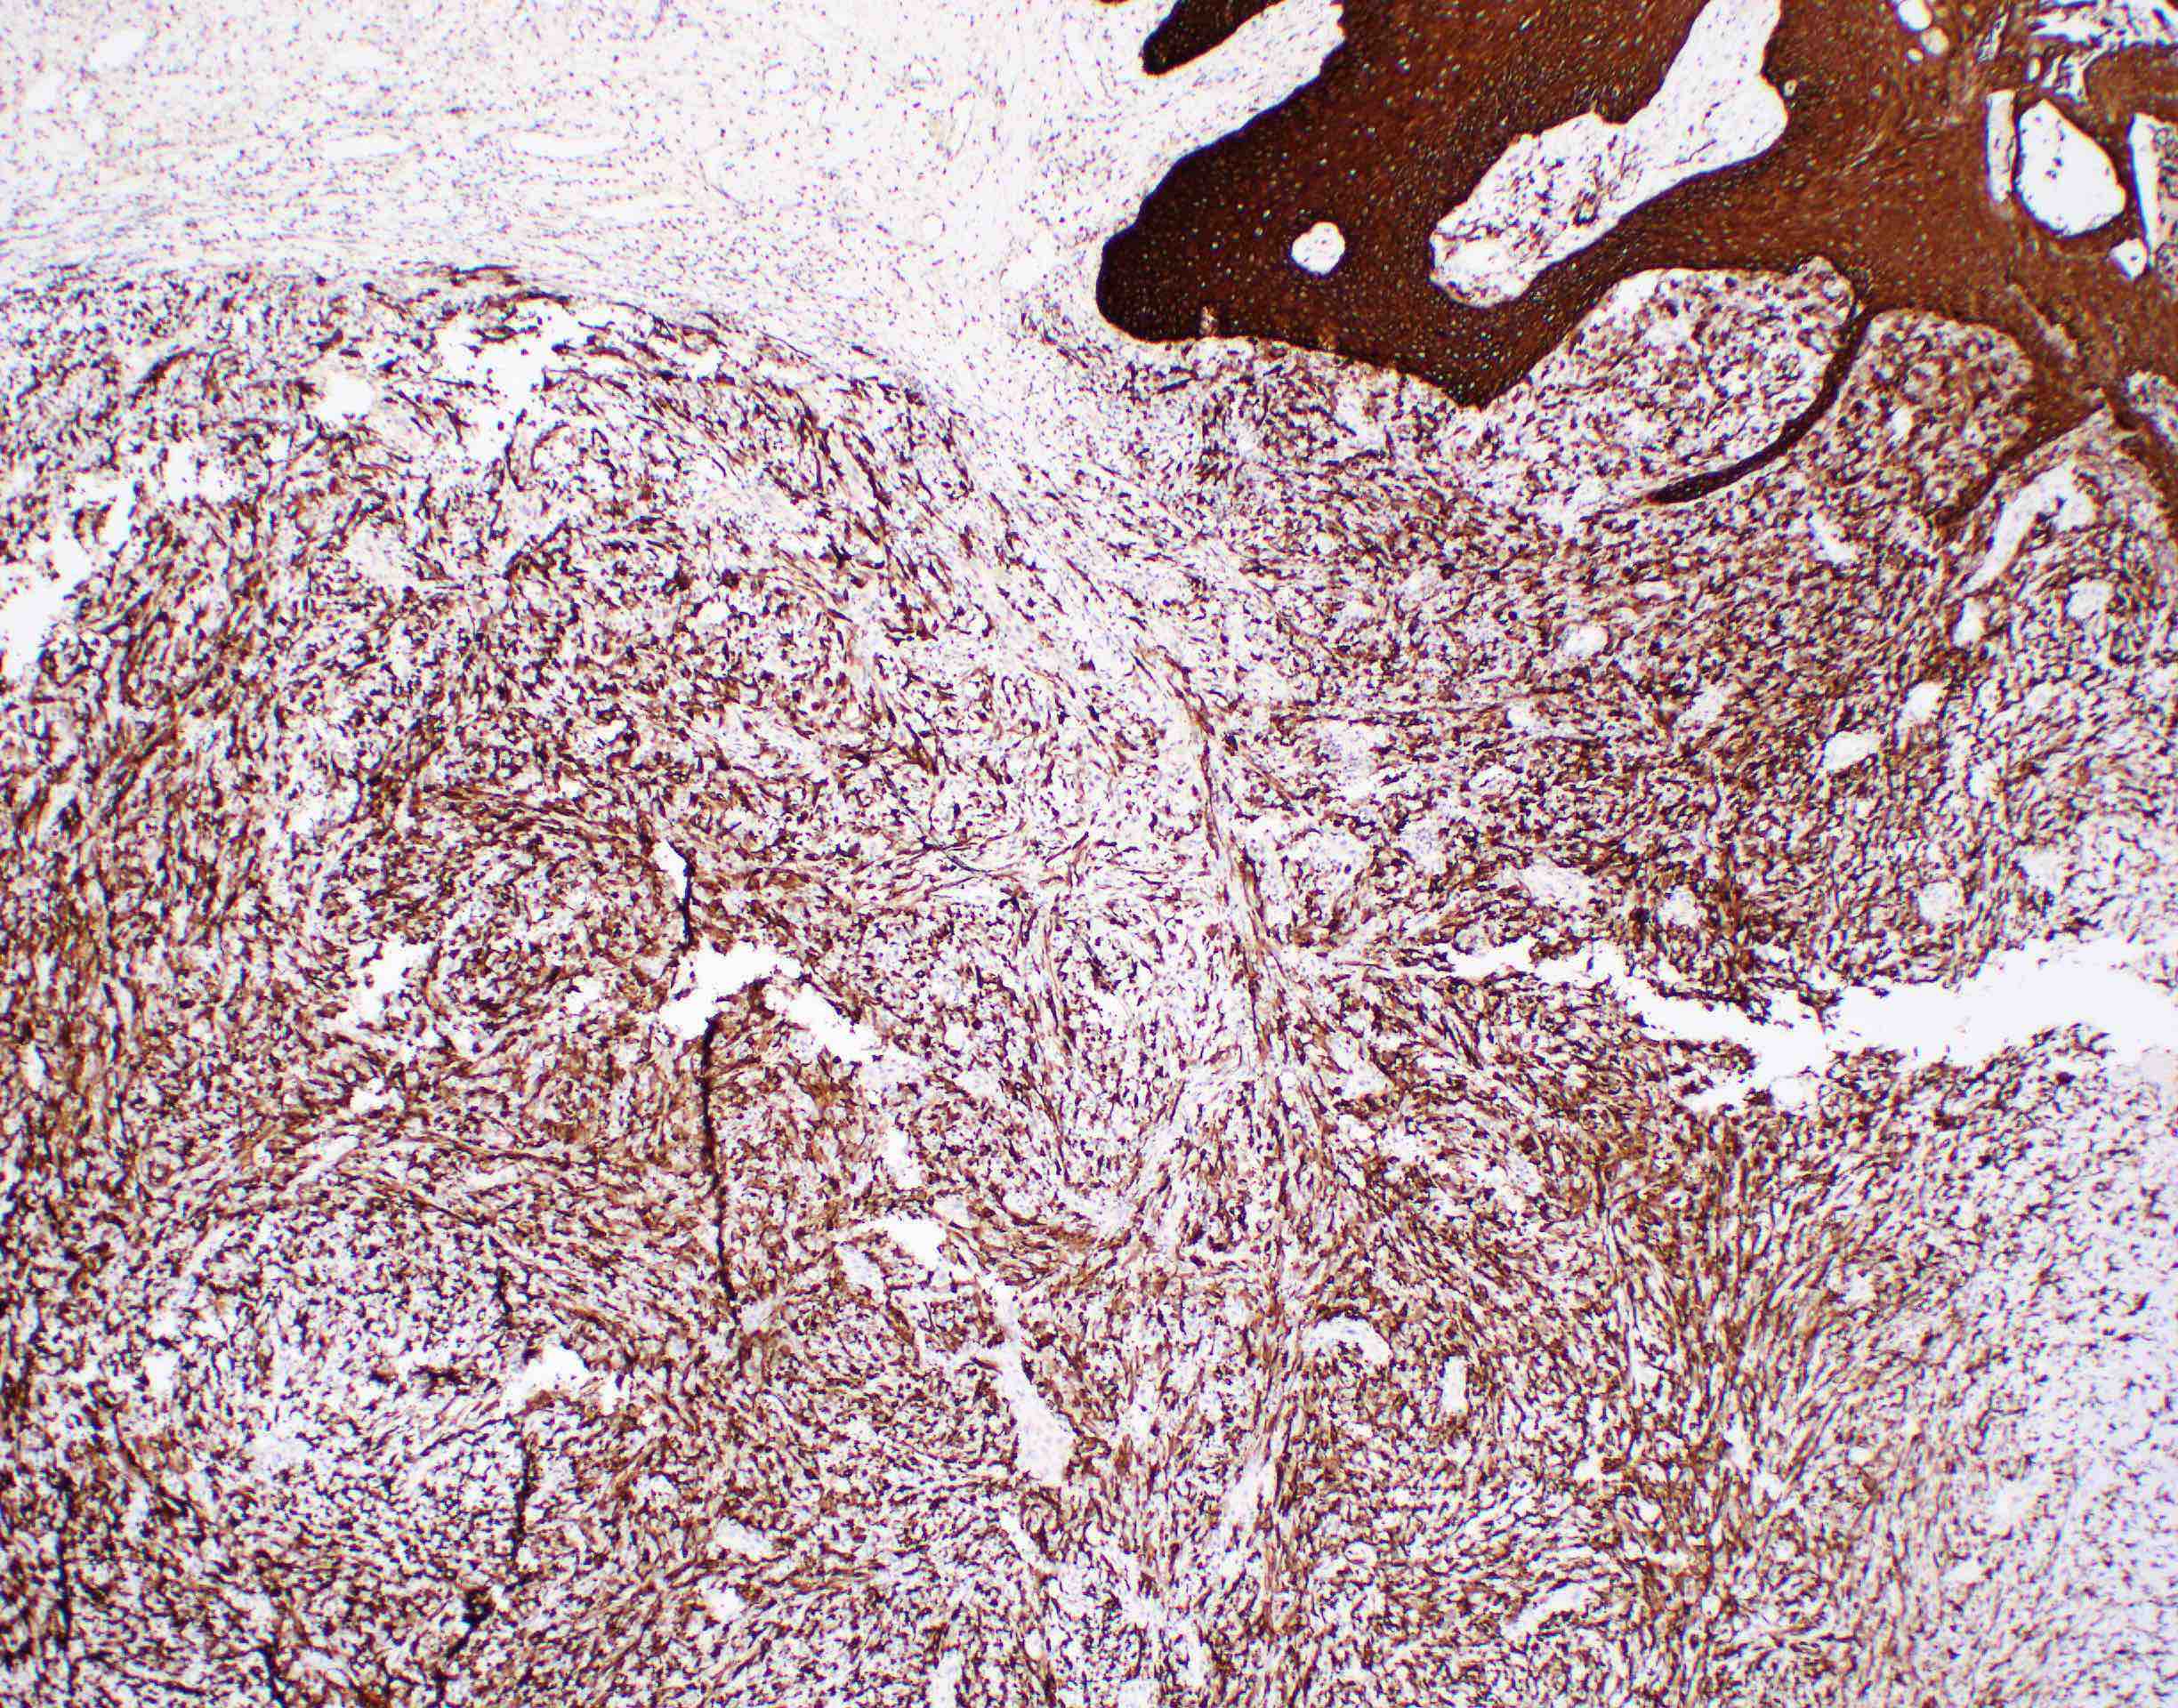

- Spindle cell / sarcomatoid squamous cell carcinoma (Am J Otolaryngol 2008;29:123)

- Most commonly occurs postradiotherapy or as second primary

- Mesenchymal in appearance

- Atypical plump spindled cells arranged in fascicles or storiform pattern

- May have metaplastic or neoplastic cartilage or bone